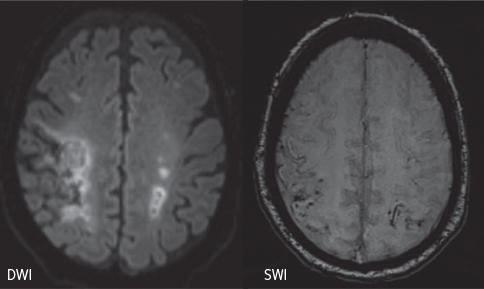

Les mécanismes de l’AVC ischémique et de la TSVC en cas de Covid-19 semblent multiples et ne sont pas tous élucidés. Comme lors de tout état infectieux, un état prothrombotique peut survenir en raison de la déshydratation, de l’inflammation avec augmentation des cytokines et activation de la coagulation.9,12 Lors d’un Covid-19 sévère, un nombre important de patients semble développer des anticorps antiphospholipides,13,14 déclenchant des micro- et macrothromboses dans plusieurs organes. En outre, une endothéliopathie liée à un tropisme du SARS-CoV-2 pour les cellules endothéliales qui expriment fortement le récepteur du virus ECA2 peut causer des thromboses (ischémies) et des hémorragies dans les petits et grands vaisseaux dans le cerveau et ailleurs,5,15 comme chez le patient sur la figure 1. Finalement, il peut y avoir une cardiopathie liée au virus sous différentes formes. On peut constater une élévation des enzymes cardiaques, une infiltration lymphocytaire, une prise de contraste de plusieurs structures cardiaques, ou encore un épanchement péricardique.